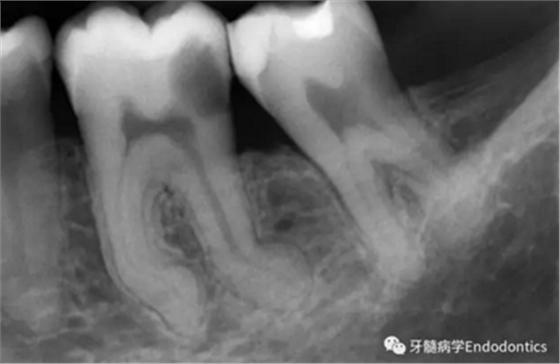

圖1.探查冠方2/3可以獲得有關(guān)根管系統(tǒng)解剖形態(tài)的相關(guān)信息,獲得根管彎曲和多重彎曲程度,或者是否存在根管彎曲的一些重要反饋。醫(yī)生需要重視五種可能遇到的根管解剖類型(包括融合、彎曲、多重彎曲、分歧、分支)。

當(dāng)建立直線通路、找到所有的根管口后,重心應(yīng)轉(zhuǎn)移到根管預(yù)備上。若牙髓存在活力且持續(xù)滲血,應(yīng)使髓室內(nèi)充滿粘性螯合劑。在牙髓已壞死的情況下,應(yīng)使用加熱的5.25%次氯酸鈉溶液沖洗并徹底充滿髓室。探查前,根據(jù)術(shù)前X線片測(cè)量并預(yù)彎小的不銹鋼銼,以順應(yīng)預(yù)估的根管長(zhǎng)度及彎曲度。使用0.02錐度的10號(hào)不銹鋼手用K銼探查根管冠方2/3。